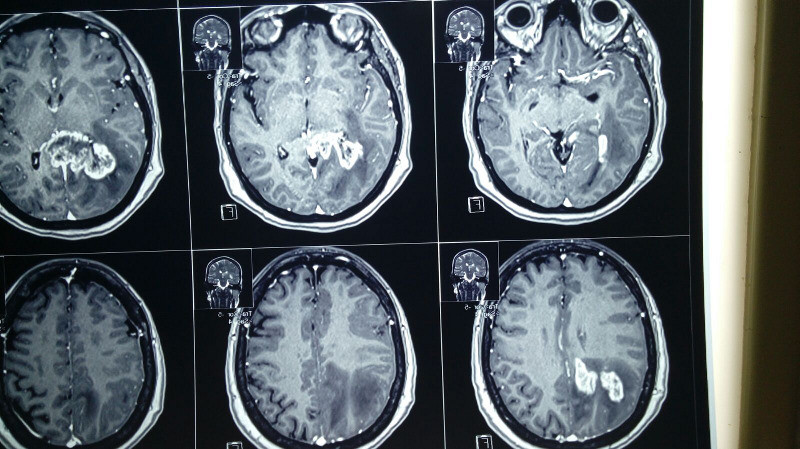

Paciente femenina de 55 años con tumoracion pineal con extencion superior lateral derecha

Espectroscopia confirma tumor cerebral